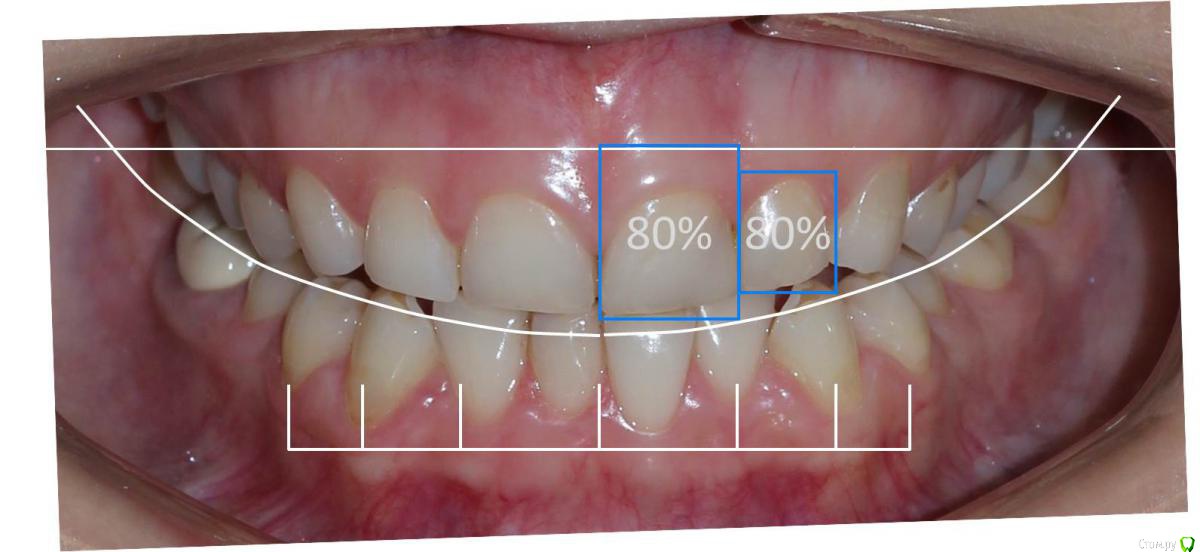

Сева северный Опубликовано 9 декабря, 2015 Поделиться Опубликовано 9 декабря, 2015 Ко мне обратилась молодая девушка, не довольная своей улыбкой. Был проведен этап планирования.... анализ улыбки ..(DSD), (wax up) и примерка (mock up)Проведенный этап...с мотивировал пациентку . 15 Ссылка на комментарий

Сева северный Опубликовано 11 декабря, 2015 Автор Поделиться Опубликовано 11 декабря, 2015 Почему не через зеркало?В принципе на вопрос уже ответили.... могу лишь добавить, что при (wax up) мы как правило воск добавляем, причем его слои, не всегда одинаковой толщины, поэтому темные зубы через (mock up) будет просвечиваться.Бывают варианты когда я наоборот не могу наносить воск+ мелкие косячки... в виде пор, фестончатых краев, небольшой ассимитрии. все это будет видеть пациент через зеркало. С расстояния.. 2-3 метра они с нивелируются. Я должен показать общую картину, именно улыбку. Сравните на прикрепленном примере... пришеечные косячки (mock up) которые я не стал исправлять, и как они не заметны на фото, с растояния 2 Ссылка на комментарий

Сева северный Опубликовано 11 декабря, 2015 Автор Поделиться Опубликовано 11 декабря, 2015 (изменено) Как вы определяете когда надо делать хир.удлинение коронки, а когда просто удлинить без хирургии. По стертым режущим краям,похоже что не было нарушения прорезывания...зондировали до ЦЭС? Или по десневой улыбке скромной решили пойти апикально?Я сделал только планирование.... Ход мысли был следующий: Длина центральных резцов 19-20 мм. Длина коронковой части зуба центрального резца 7-8 мм. Оптимальная длина 10.5. По результату пациентка с мотивирована на ортодонтию , с коррекцией gammy smile. Решение по хирургии, примем по результатам ортодонтии. Изменено 11 декабря, 2015 пользователем Сева северный 1 Ссылка на комментарий